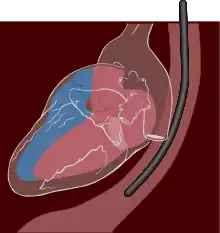

Il s’agit avant tout d’une échographie (méthode d’imagerie par ultrasons). La sonde d’échographie utilisée a la forme d’un tuyau souple qui passe par la bouche puis le pharynx et enfin l’œsophage. Le but principal de cet examen est d’obtenir des images des zones du cœur difficilement accessibles par la technique plus courante de l’échocardiographie transthoracique. Les zones concernées sont principalement l’atrium gauche et la paroi postérieure du ventricule gauche. La visualisation de l'atrium gauche est particulièrement intéressante pour la recherche d’anomalie de cette cavité cardiaque (hypertrophie atriale gauche, présence d’un thrombus intracavitaire).

L'examen est fait sur un patient allongé sur le côté gauche, ou parfois en position assise. Un "cale-dents", dispositif en plastique empêchant la fermeture de la mâchoire, est mis en place et la sonde est introduite dans la bouche, puis dans l'œsophage du patient par l'examinateur.

Les structures postérieures du cœur sont beaucoup mieux visualisées au cours d'une échographie trans-œsophagienne que d'une échographie classique. C'est, en particulier, le cas des valves cardiaques, surtout mitrale et aortique, de l'atrium gauche, de l'aorte thoracique dans toutes ses parties.